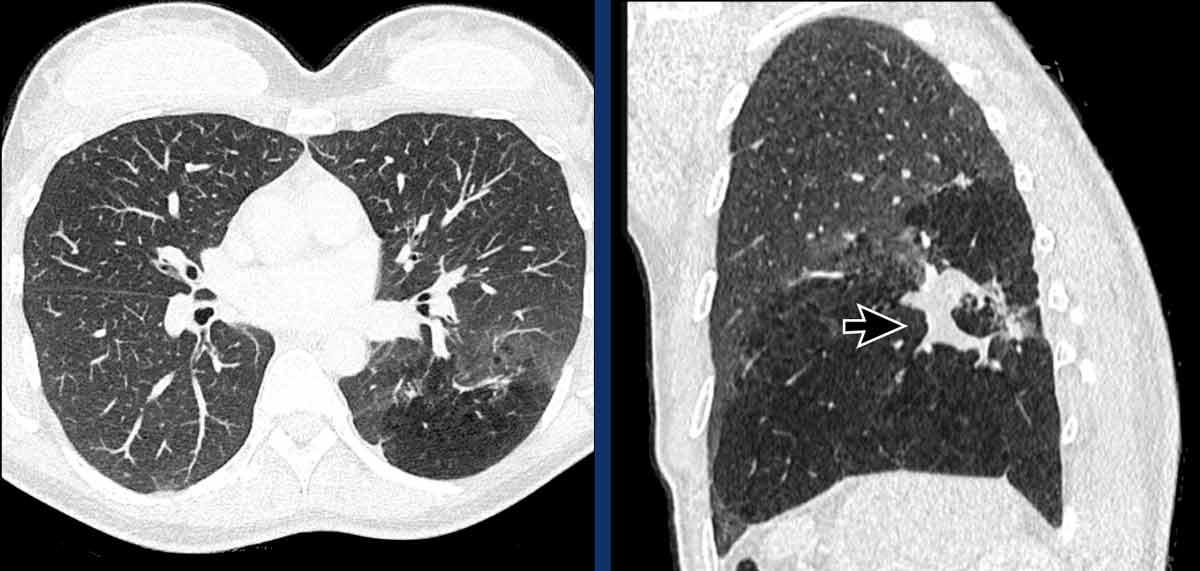

Teo phế quản ở thùy dưới phổi trái ở nữ giới 47 tuổi.

Cấu trúc phân nhánh điển hình với nhu mô phổi sáng xung quanh, đại diện cho phế quản giãn rộng chứa đầy chất nhầy (mũi tên).

Không có lỗ vào của phế quản phân thùy đáy sau (LB10) và ứ khí lan rộng của nhu mô phổi liên quan, thấy rõ nhất trên các tái tạo phổi.

Tiếp tục với hình ảnh tiếp theo…

Hình ảnh MIP (chiếu cường độ tối đa) lát dày cho thấy các đường thở giãn rộng chứa đầy chất nhầy ở thùy dưới phổi trái (mũi tên).